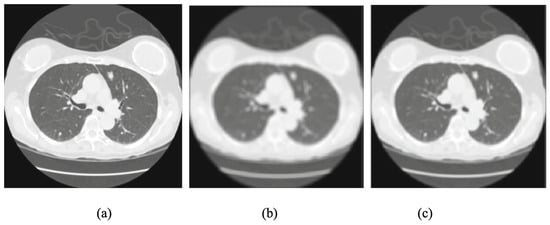

4. Image Preprocessing

- Hofmanninger, J.; Prayer, F.; Pan, J.; Röhrich, S.; Prosch, H.; Langs, G. Automatic lung segmentation in routine imaging is primarily a data diversity problem, not a methodology problem. Eur. Radiol. Exp. 2020, 4, 1–13. [Google Scholar] [CrossRef] [PubMed]